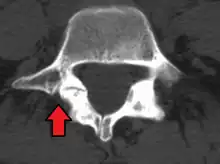

Anterolisthesis L5/S1. Blue arrow normal pars interarticularis. Red arrow is a break in pars interarticularis -

Anterolisthesis L5/S1